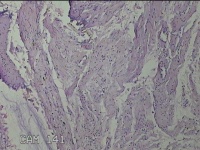

子宫体肌瘤结节

性别

女

年龄

32岁

临床诊断

子宫肌瘤 疤痕子宫

一般病史

发现子宫肌瘤数月余。

标本名称

大体所见

灰白色圆柱形条索状组织10x7.5x1.8㎝一堆,切面均为灰白色结节状或编织状,质中。